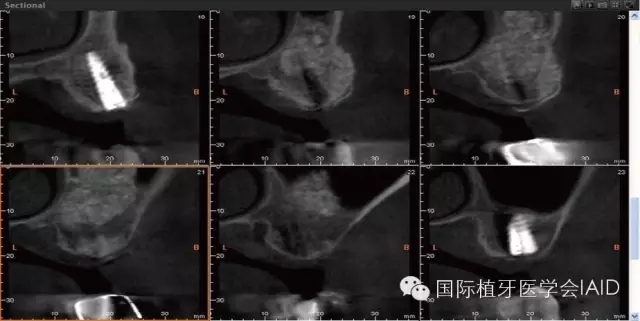

在植牙手術(shù)執(zhí)行之前,需要進(jìn)行全口檢查與軟硬組織的評(píng)估??谕馐嗄P团ccone beam CT資料搜集有助于治療計(jì)劃的擬定。在石膏模型上進(jìn)行diagnostic wax up有助于決定植體上假牙前后關(guān)系、頰舌側(cè)位置、咬合高度、及植體與植體上假牙的高度比例。使用Cone beam CT(CBCT)可以容易了解手術(shù)區(qū)硬組織條件,如Septum、骨頭高度及寬度、骨頭密度、神經(jīng)血管位置等。分析以上數(shù)據(jù)后,較容易得到可預(yù)期性的結(jié)果。

初期穩(wěn)定度在第一及第二類型的案例(>9mm; 6mm-9mm) 可以較容易達(dá)到,故通常以crestal approach進(jìn)行手術(shù)。Lateral window術(shù)式在第三型(3mm-6mm)較被建議。 若是前三個(gè)類型的初期穩(wěn)定度達(dá)到35Mpa,可以考慮當(dāng)次放置植體。若骨頭條件屬于第四型(<3mm),Lateral approach 比較建議使用,而植體可考慮等到Grafted Bone較成熟時(shí)再置入。(Fig. 1 & 2)術(shù)式的選擇與骨頭高度有密切的關(guān)系,當(dāng)骨頭垂直高度小于3 mm(于兩顆植體中),植體應(yīng)考慮 Bone graft穩(wěn)定后再植入。

Lateral window的區(qū)域及范圍可借由CBCT和解剖構(gòu)造位置來(lái)決定。理想的window骨切線前緣及下緣位置應(yīng)離sinus底部(floor)其前緣(anterior wall)3-5 mm (Fig. 5 & 6)。